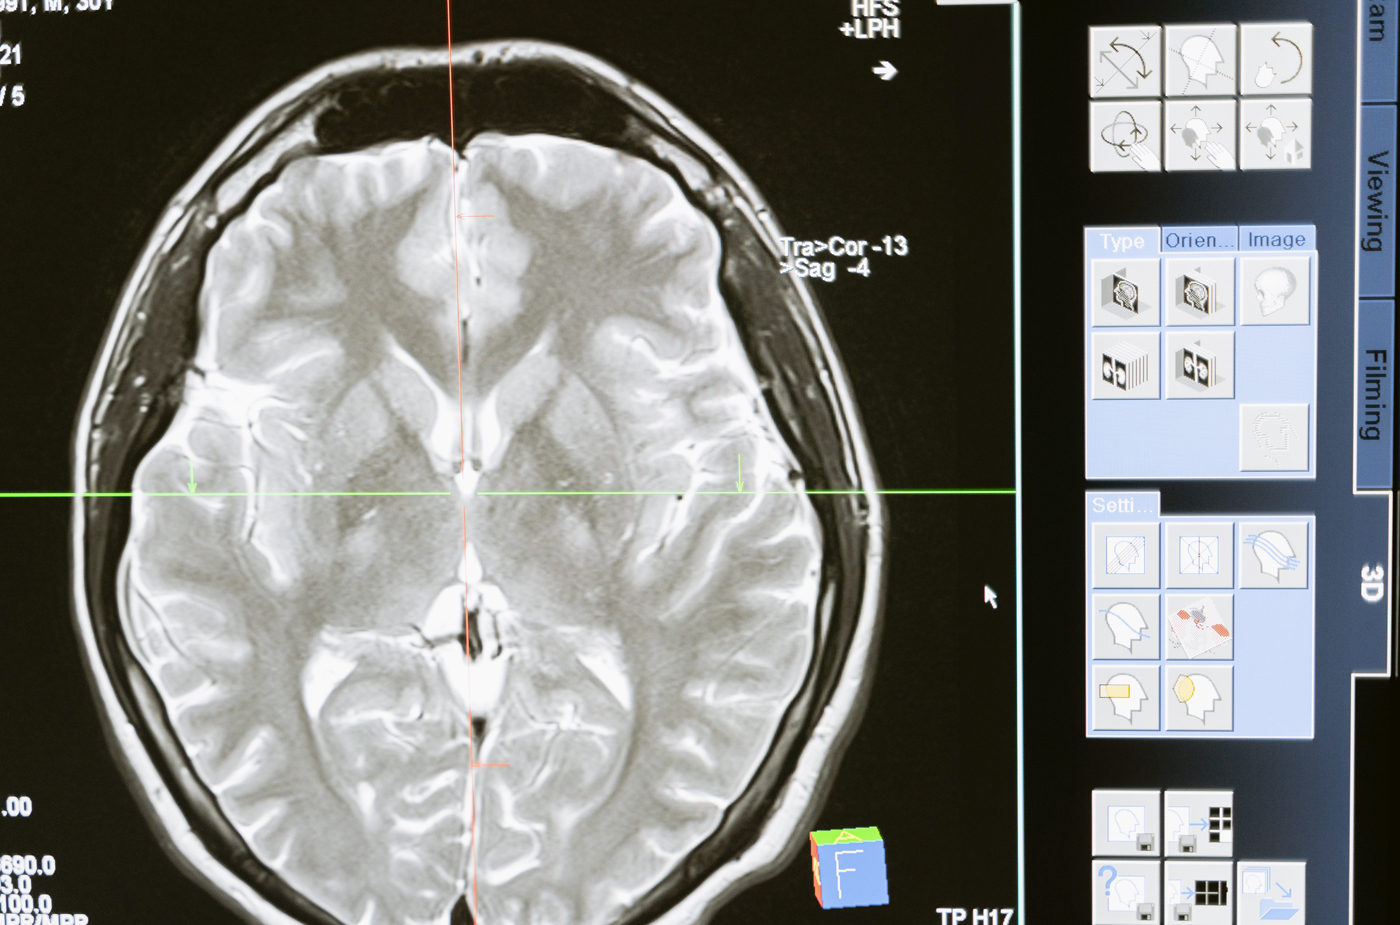

Afin de détecter une méningite, il faut réaliser une ponction lombaire pour prélever un échantillon de liquide céphalorachidien à analyser. Un examen de sang peut aussi être nécessaire pour identifier la bactérie responsable dans le cas d’une méningite bactérienne.

Diagnostiquée tardivement, la méningite peut entrainer de graves complications telles que la formation de caillots, un œdème cérébral, une augmentation de la pression dans le crâne et même la mort du malade.

Lorsque l’issue n’est pas fatale, le malade peut s’en sortir avec des séquelles telles que des lésions du cerveau, une perte de l’audition ou des troubles de l’apprentissage.